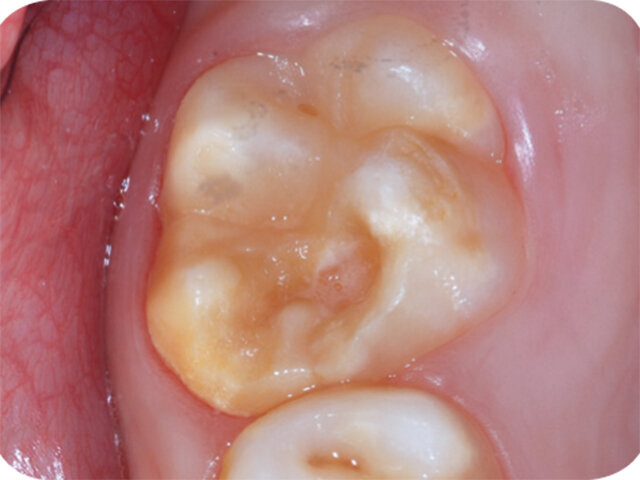

Molárová a incizální hypomineralizace skloviny (Molar Incisor Hypomineralisation – MIH) je globální problém postihující každé sedmé dítě. MIH je běžná vývojová porucha postihující především jeden nebo více prvních stálých molárů. Centrální řezáky mohou být rovněž postiženy, většinou však v menší míře. Může též dojít k hypomineralizaci druhých dočasných molárů (Hypomineralised Lesions on Second Primary Molars – HSPM, hypomineralizační léze druhých stálých molárů) nebo špičáků. U dětí s HSPM je až pětkrát vyšší pravděpodobnost vzniku MIH u stálého chrupu. Závažnost se velmi liší od mírných opacit k posterupčnímu odlomení skloviny.

Klinický vzhled

- Ohraničené opacity v rozpětí od krémově bílé, přes žlutou až po hnědé diskolorace

- Poškozená sklovina má normální tloušťku (dokud nedojde k posterupčnímu odlomení skloviny)

- Léze se mohou vyskytovat asymetricky

- Je-li závažně poškozen první molár, existuje zvýšená pravděpodobnost, že protilehlý molár bude rovněž poškozen